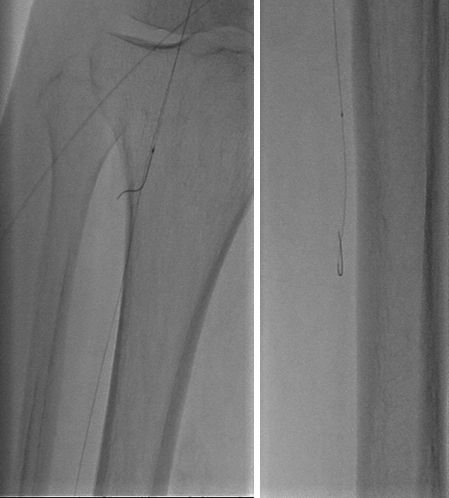

逆行技术

Trans-luminal

From no-target artery

Through pedal arch or ACA/PCA

To distal cap of CTO in target artery

Transcutaneous

Surgery exposure

Puncture